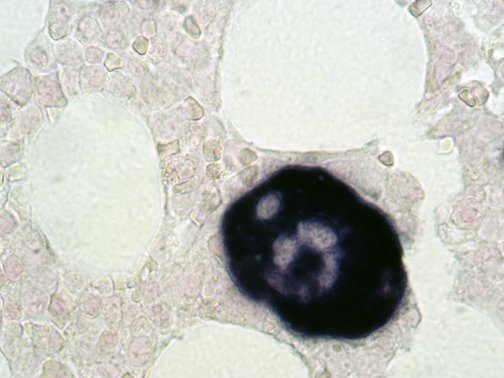

Clinical and laboratory manifestations of HLH include fever, enlarged liver and/or spleen, neurologic dysfunction, coagulopathy, liver dysfunction, cytopenias (i.e., low levels of erythrocytes, leukocytes, and/or platelets), hypertriglyceridemia, hyperferritinemia, hemophagocytosis, and eventually diminished NK cell activity as the immune system becomes progressively paralyzed. HLH can be familial (primary HLH) or secondary to another disease process (sHLH), such as rheumatic disease, in which it is referred to as macrophage activation syndrome (MAS, characterized by elevated ferritin).